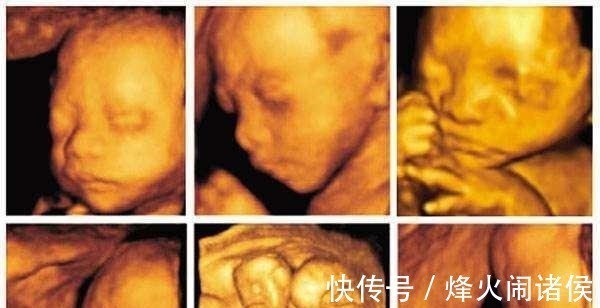

胎盘|四维彩超那么贵, 不懂这些就白做了 3分钟让读懂报告单!

无论你现在是否已经怀孕了,产检的重要性都是知道。前几天我给大家分享了如何看懂尿检单和血检单。是不是还有一个一个关键的产检报告单还没有和大家分享呢?那就是四维彩超的报告单了。我们都知道思维彩超价格高,检核和排畸效果也最好。但是看着报告单上的数据,你有没有还是傻傻分不清楚啊。

2、如何看懂四维彩超单这才是重头戏,对不对啊。下面我们就来分享四维彩超除了排畸外,我们应该看那些重要数据: